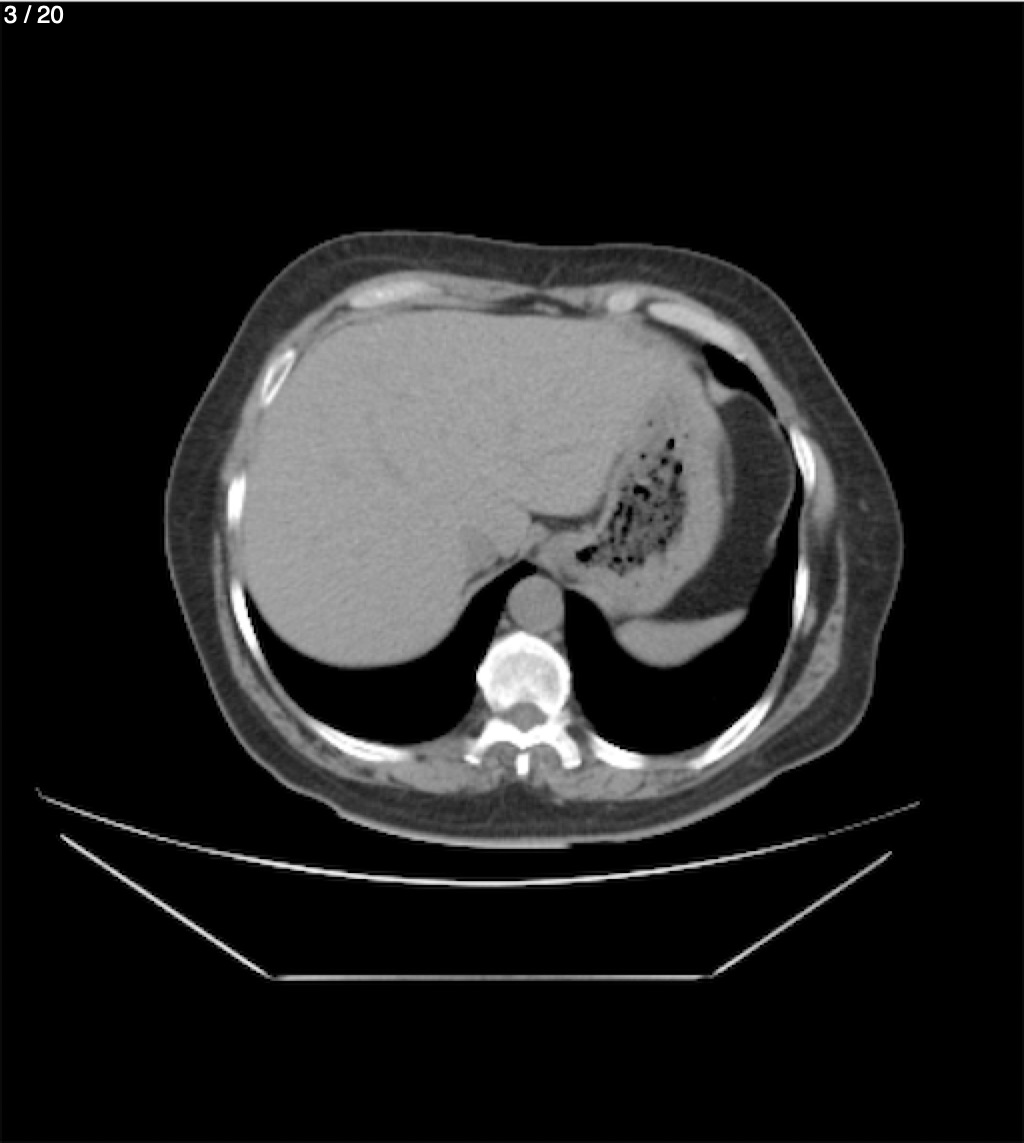

Maria Enrique Giron Dominguez63A - T.C Abdomen Simple